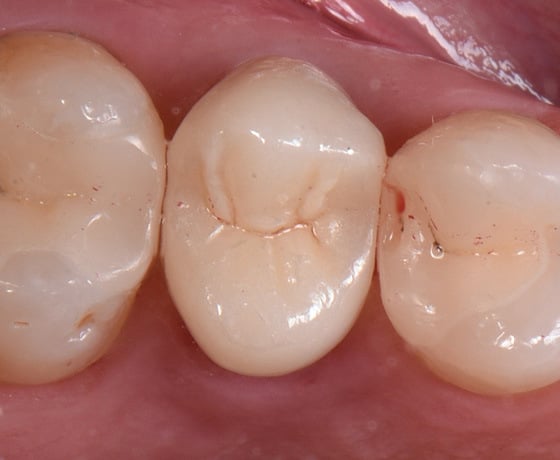

Situazione iniziale e isolamento del campo con diga di gomma.

Restauri parziali dei molari e dei premolari superiori aderenti.